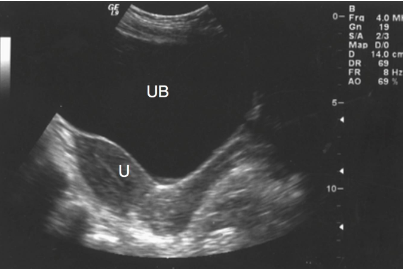

What is the echogenicity of the bladder?

Anechoic